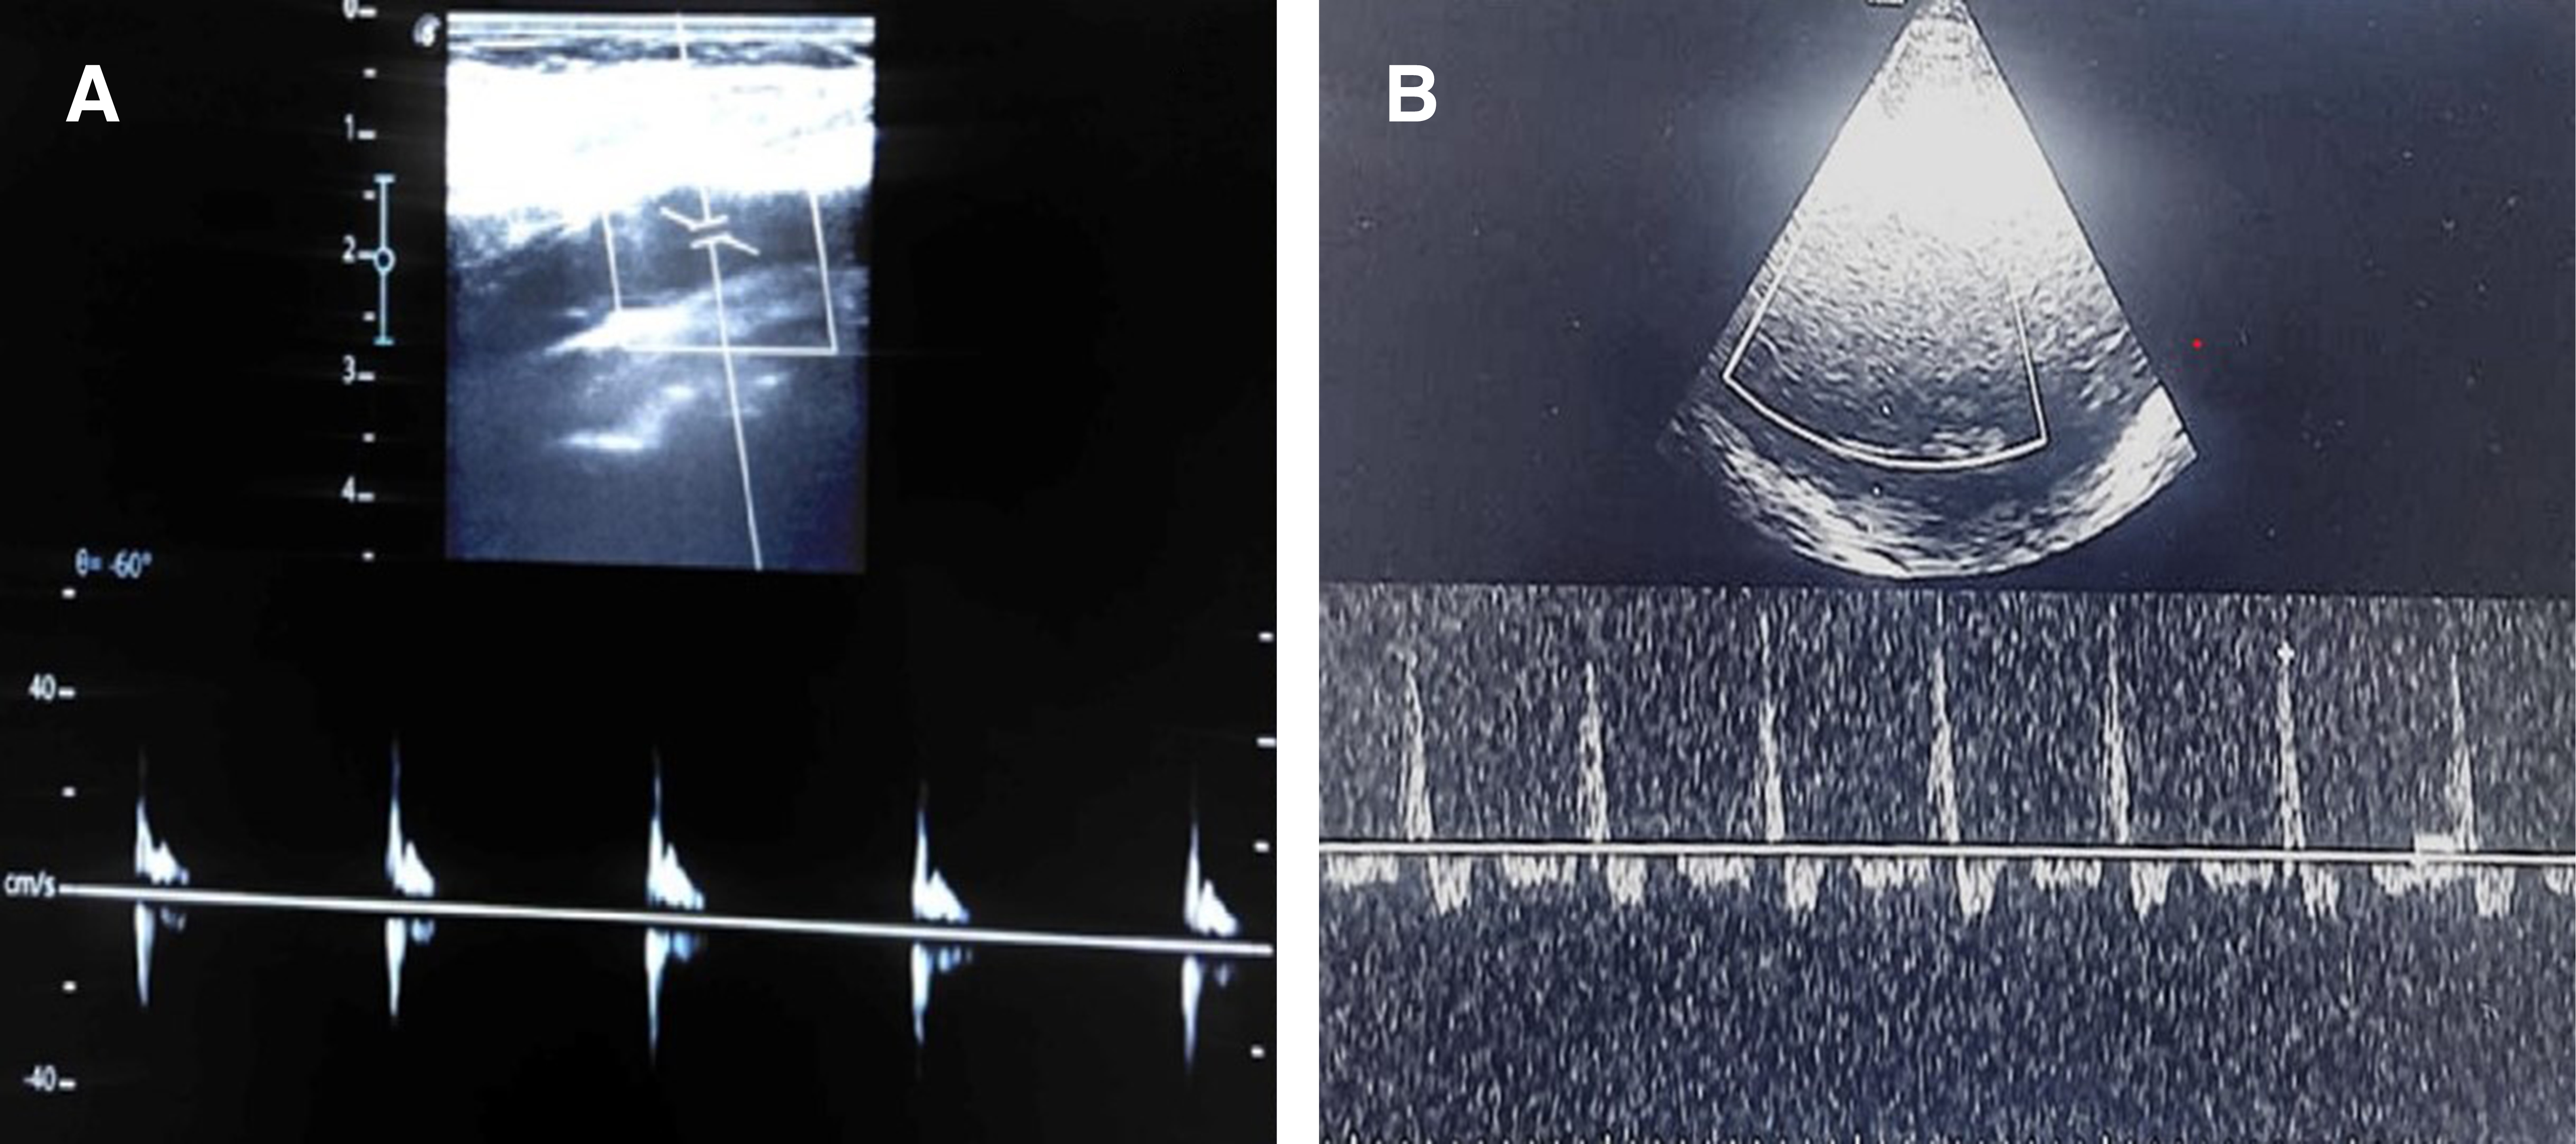

Patrones diagnósticos de MC por DTC. En la MC pueden observarse los siguientes patrones de flujo en el DTC: 1) oscilación sistólica y diastólica con flujo sistólico anterógrado y diastólico retrógrado debido a una obstrucción distal, 2) espigas sistólicas de duración menor de 200 ms con velocidad menor de 100 cm/s sin señal de flujo en el resto del ciclo y 3) ausencia de flujo en las arterias cerebrales (Figura 1),3,5,6 que de encontrarse en todas las arterias de la base del cráneo correlacionan con amputación del FSC en la arteriografía cerebral con 100% de especificidad.1

Caso 1. Hombre de 17 años que es traído por personal prehospitalario a la sala de emergencias el 19 de diciembre de 2021 tras sufrir un accidente de motocicleta con diagnóstico de lesión cerebral traumática. A su ingreso presenta pupilas de 4 mm de diámetro y reflejo fotomotor disminuido con un puntaje en la escala de coma de Glasgow de 7, se realiza secuencia de intubación rápida y ventilación mecánica invasiva, en la tomografía de cráneo se observa un hematoma epidural parietoccipital derecho que desvía la línea media hasta 10 mm más hemorragia cerebelosa derecha con compresión del tallo cerebral. El estudio de gases arteriales se reporta un pH de 7.5 y presión parcial de dióxido de carbono arterial de 21 mmHg. El día 20 de diciembre presenta midriasis bilateral y ausencia de reflejo fotomotor, por lo que se inicia protocolo de MC, se retira la sedación y se realiza DTC, en el cual se observa ausencia de flujo en el polígono de Willis en ventana transtemporal bilateral por dos observadores entrenados, posteriormente se realizó un ultrasonido Doppler en ACC y ACIe observando espigas sistólicas de 45 cm/s con patrón oscilante y ausencia de flujo diastólico (Figura 2). La MC se corroboró por angiotomografía cerebral. Los familiares no aceptan donación de órganos, por lo que se retira el soporte multiorgánico.

Caso 2. Mujer de 63 años con antecedente de diabetes e hipertensión arterial sistémica, admitida en la unidad de cuidados intensivos (UCI) el 30 de noviembre de 2021 por COVID-19 crítico con síndrome de distrés respiratorio agudo severo. La paciente fue sometida a traqueostomía el día 17 de diciembre por ventilación prolongada y ese mismo día presenta secreciones bronquiales abundantes y coágulos que ocasionan obstrucción en la vía aérea y arresto cardiaco por hipoxia por aproximadamente cuatro minutos, posterior al retorno de la circulación espontánea presenta hipoxemia sostenida con saturación de oxígeno arterial (SpO2) de 80% a pesar de una fracción inspirada de oxígeno al 100% y presión positiva al final de la espiración de 8 cmH2O. La paciente es encontrada durante la guardia nocturna del 20 de diciembre con midriasis bilateral de 8 mm de diámetro sin reflejo fotomotor, por lo que se inicia protocolo para descartar MC. Se realiza USG en la ACC, observando espigas sistólicas con velocidad de 45 cm/s y patrón oscilante con ausencia de flujo diastólico, posteriormente se realiza DTC, en el cual se observa ausencia de flujo en el polígono de Willis y circulación posterior corroborando la MC (Figura 3). La paciente no es candidata a donación de órganos por disfunción multiorgánica, por lo que se suspende el soporte de vida.

En los casos expuestos anteriormente identificamos imágenes con patrones ecográficos similares a los descritos por Yoneda y colaboradores observando en el espectro Doppler flujo diastólico retrógrado a nivel sólo de la ACC, a diferencia de Mehrdad y su equipo que también analizaron la ACIe aumentando la sensibilidad para el diagnóstico de MC. En nuestros casos corroboramos el patrón descrito de forma bilateral a nivel de las ACC y las ACIe encontrando picos sistólicos anterógrados de baja velocidad y ondas diastólicas retrógradas de velocidad aún menor.